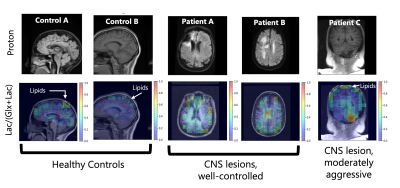

Representative anatomical scans and Lac/(Glx+Lac) maps from all five scan subjects – two healthy controls, two well-controlled CNS lesions, and a moderately aggressive CNS lesion. Healthy controls do not show elevated lactate, though natural-abundance signal from the lipids have overlapping resonances. The well-controlled CNS lesions (Patients A & B) have decreased Glx from necrotic regions of their lesions. The more aggressive lesion in Patient C has an elevated Lac/(Glx+Lac) signal around the lesion, potentially indicative of the Warburg effect.

Representative metabolic maps, corresponding anatomical scans, and example spectra of a healthy control, a patient with a well-controlled CNS lesion (Patient A), and a patient with a more aggressive CNS lesion (Patient C) are shown in Figures 1, 2 and 3 respectively. Figure 4 compares the Lac/(Glx+Lac) fraction across all five subjects. 3D whole-brain coverage is achieved in these DMI scans, including areas typically plagued by inhomogeneities in proton MRS such as near the brainstem. Good anatomical correspondence between the cerebrospinal fluid and lowered 2H-Glx is notable in the healthy control (Figure 1). Patient A shows a decrease in 2H-Glx in the necrotic region of the lesion without a corresponding increase in 2H-Lac (Figure 2). Patient C shows decreased Glx as well in the necrotic region of the lesion, with a moderate increase in Lac as seen most clearly on the Lac/(Glx+Lac) map (Figure 3). All patients show an elevated “Lac” signal near the skull due to partial voluming from the natural abundance 2H-lipid peaks overlapping the lactate resonance.